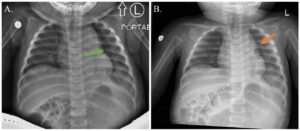

Incarcerated Gastric Volvulus and Splenic Herniation. Chest Radiographs on Postoperative Days 1 and 4. Annotated. JETem 2025